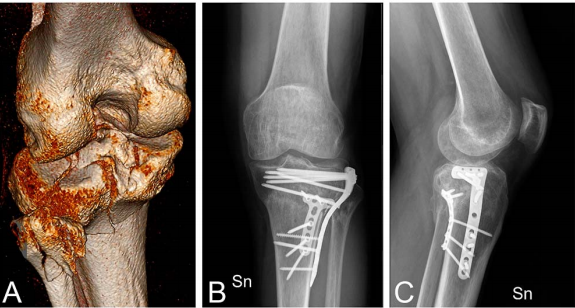

图 5一名受左胫骨平台后外侧骨折影响的 28 岁男性患者的术前 CT 扫描 (A)。1 年时的前后位 (B) 和侧位 (C) X 光片显示通过同一改良 Frosch 入路进行的双钢板固定(后外侧和前外侧)和后路植骨,具有优异的影像学结果。